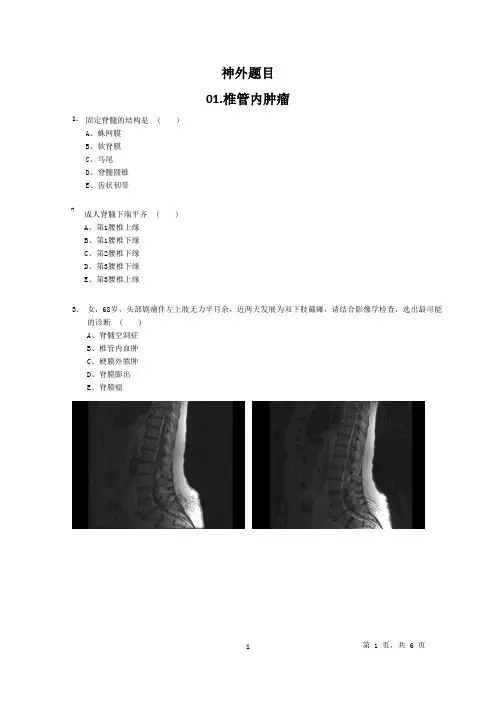

神外题目01.椎管内肿瘤1. 成人脊髓下端平齐 ( )A 、第1腰椎上缘B 、第1腰椎下缘C 、第2腰椎下缘D 、第3腰椎下缘E 、第3腰椎上缘固定脊髓的结构是 ( )A 、蛛网膜B 、软脊膜C 、马尾D 、脊髓圆锥E 、齿状韧带2. 女,68岁,头部剧痛伴左上肢无力半月余,近两天发展为双下肢截瘫,请结合影像学检查,选出最可能的诊断 ( )A 、脊髓空洞症B 、椎管内血肿C 、硬膜外脓肿D 、脊膜膨出E 、脊膜瘤3.男,27岁,常有手、臂的自发性疼痛、麻木、蚁走等感觉异常,结合MRI 检查选择最可能的诊断 ( )A 、脊髓软化B 、脊髓空洞症C 、脊髓内胶质瘤D 、脊髓内室管膜瘤E 、神经鞘膜瘤4.硬脊膜外隙 ( )5.A、是硬脊膜与椎管内面的骨膜之间的空隙B、向上与颅的硬膜外隙相通C、是硬脊膜与蛛网膜之间的腔隙D、有脊神经前支通过E、内含脑脊液楔束传导 ( )6.A、温度觉B、痛觉C、味觉D、精细触觉E、轻微触觉以下对侧柱的描述正确的是 ( )7.A、位于腰1至腰5脊髓侧角B、是交感神经节前神经元胞体所在的部位C、是副交感神经节后神经元胞体所在的部位D、仅见于胸脊髓节段E、传导内脏感觉对脊髓被膜的描述,错误的是 ( )8.A、蛛网膜下隙与颅内蛛网膜下隙和终池相通B、硬脊膜下隙位于硬脊膜与蛛网膜之间潜在的腔隙下隙C、蛛网膜与软脊膜间为蛛网膜下隙D、硬脊膜外隙与颅内硬膜外隙相通E、硬脊膜外隙位于硬脊膜与椎管壁之间对脊髓灰质描述正确的是 ( )9.A、后角只存在于颈髓B、交感神经节前神经元的胞体位于胸髓和上腰3节内的侧角C、腰骶膨大段前角发达D、副交感神经节前神经元的胞体位于骶尾段E、前角仅见于胸髓对脊髓的描述正确的是 ( )10.A、直接被软脊膜包裹B、由灰质、白质组成C、直接被脑脊液包裹D、终丝由神经纤维组成E、直接被蛛网膜包裹有关薄束的说法正确的是 ( )11.A、位于脊髓前索B、传导同侧上肢浅感觉C、起自对侧脊髓后柱固有核D、只见于脊髓胸、腰段E、传导同侧下肢本体觉对脊髓颈膨大的描述,正确的是 ( )12.A、与颈部的肌肉发达有关B、该节段含神经纤维较多C、仅连于臂丛D、位于第4颈节与第1胸节之间E、发出颈丛男性,30岁,腰背痛1年,双下肢无力2个月。